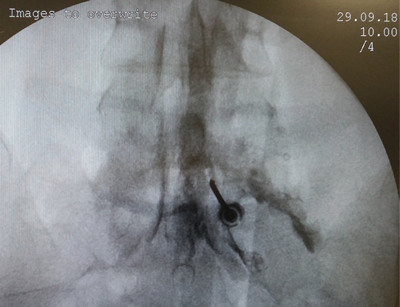

Tablas y Figuras

Figura 1